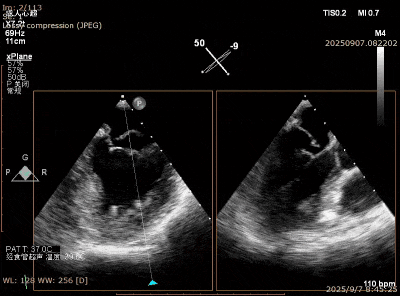

在经股静脉途径的TEER手术时,房间隔穿刺是一个很重要的基础步骤。有时候房间隔组织较韧较厚(多见于房间隔短穿刺位置需要靠后,或者外科房间隔修补术后),穿刺针通过之后要通过导引大鞘(GC)存在着较大困难,若强行推送大鞘可引起房间隔撕裂到左心房顶引起灾难性心包填塞。传统做法时使用外周球囊对房间隔进行扩张,但是不是每个导管室都常规配备外周球囊,且使用过大球囊仍可引起房间隔撕裂风险。我们提供了一种更简洁的方式,即使用导引鞘内芯和房间隔穿刺鞘两个管子(双管齐下)同时扩张房间隔穿刺口,再推送导引大鞘通过房间隔,无需额外器械,操作简单高效且安全(图1-4)。

图2. 从房间隔穿刺鞘里送入两根Lunderquist 超硬导丝

图3. 沿着两根加硬导丝送入导引鞘内芯和房间隔穿刺鞘对房间隔进行扩张

图4. 顺利送入导引鞘通过房间隔